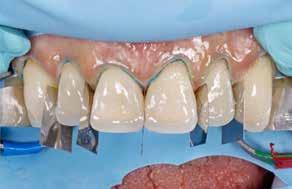

Behandlingsplan og behandling indbefatter IOS og sammenbid med leaf gauge, indtil posteriore kontakter ophæves, og der ses ca. 2 mm luft mellem molarer, svarende til ca. 4-5 mm plads i fronten. Der tages fotoserie og laves smiledesign i Smilecloud, som deles med teknikeren sammen med IOS. Teknikeren laver digitalt wax-up af 3,2,1+1,2,3 og 3,2,1-1,2,3 ud fra smiledesignet og tandlægens instruktioner. Herefter printes modeller og klare siliconestents til plastopbygning i overkæben (Fig. 8 A).

Underkæbefronten bygges op i fri hånd. Der anvendes kofferdam (Fig. 7 D, E, F, G). Vi anvender nanohybrid kompositplast

A1 (Venus® Diamond Kulzer, US) på alle slidflader posteriort samt palatinalt i overkæbefronten (Fig. 8 B, C). I det æstetiske område facialt på 3,2,1+1,2,3 og 3,2,1-1,2,3 anvendes dentin og emaljeflowplast (GC Essentia Light Dentin, Gaenial Flow samt Bleach White og GC Light Enamel, GC) (Fig. 8 D). I overkæbefronten bygges hver anden tand op ud fra stent. Dette gøres i Venus Diamond A1. Herefter laves facialt cut back og direkte layering med Light Dentin, tints og afsluttende Light Enamel (Fig. 8 C, D). Efter indslibning i okklusion og artikulation bygges tænderne op posteriort i fri hånd med overdækning af svækkede cuspides. Efter endelig justering af okklusion og artikulation (Fig. 8 E, F) samt polering til efterfølgende kontroller (Fig. 8 G, H) fremstilles hård bidskinne med fuld balanceret kontakt til natlig brug.